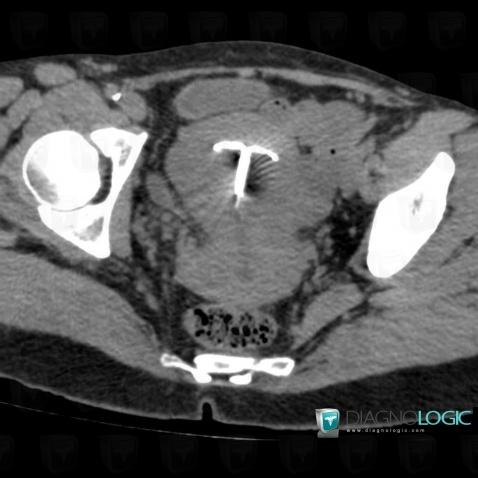

Intrauterine device, Uterus, CT

Here is the specific information in the key image above:

- Diagnosis Intrauterine device, Location(s) Uterus, with gamuts